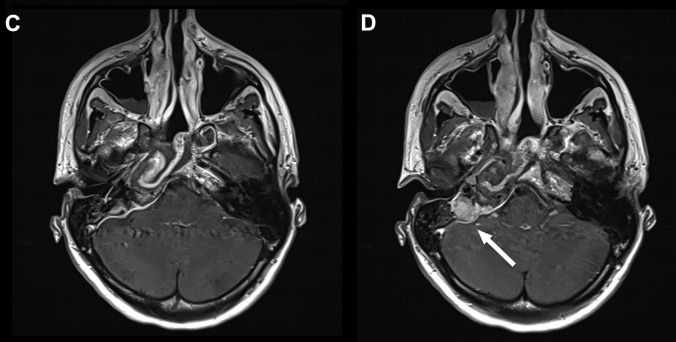

术前(红色区域):A、C图位于蝶鞍中央的9mm垂体微腺瘤。B图表示计算机断层扫描仪显示了蝶窦的鞍周型气管化。

手术过程:使用筷子手法进行广泛的蝶窦切开术,从手术区域清除血液并解剖假包膜平面,进而完整地切除肿瘤(不分块切除,防止肿瘤残留)

术后(蓝色区域):D图显示垂体瘤被肉眼下完整切除,且完成内分泌治疗。